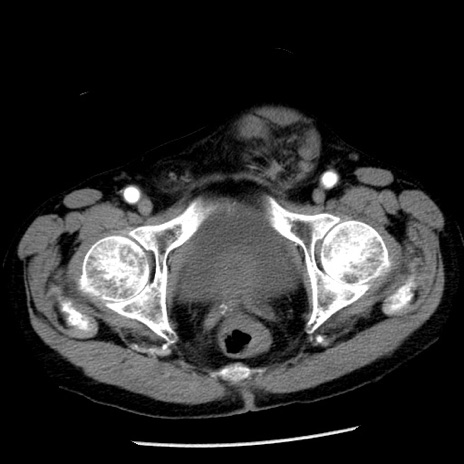

症例26(横断像)

【症例】80歳代男性

【主訴】嘔吐

【現病歴】昨晩2回嘔吐あり、今朝になっても嘔吐あり。来院。

【既往歴】胃潰瘍

【身体所見】意識清明、BT 37.6℃、BP 166/95mmHg、HR 100bpm、SpO2 97%、腹部:平坦・軟、腸蠕動音聴取良好、圧痛なし。

【データ】WBC 21900、CRP 1.46